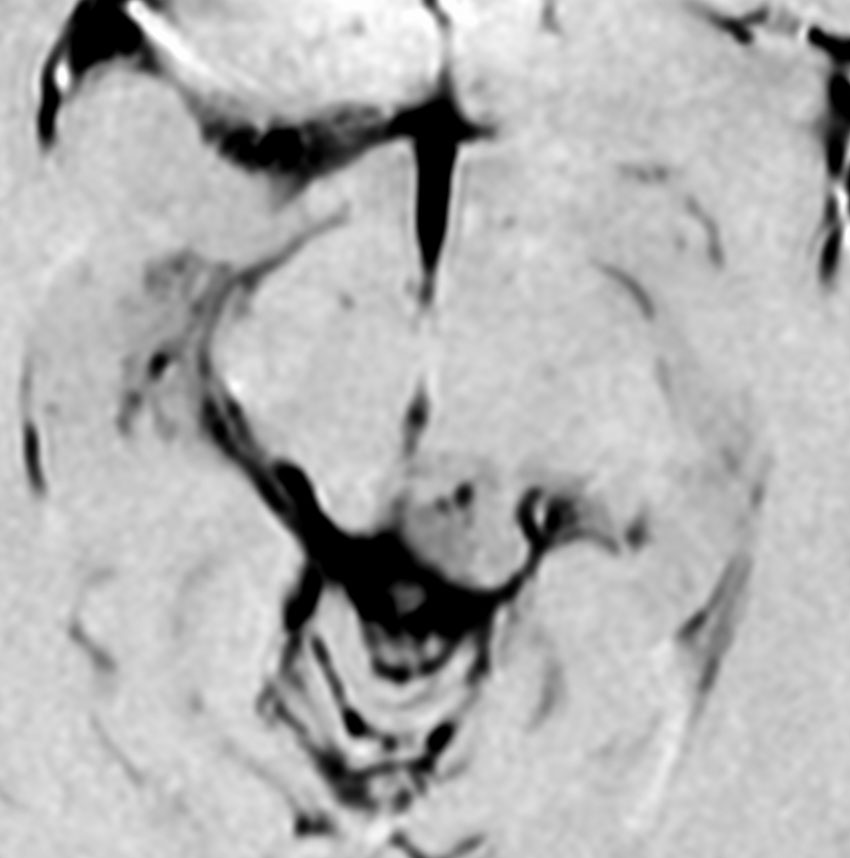

これも偶然発見された無症状の女性の小さい松果体細胞腫ですが,ほとんど実質性でのう胞がありません。右はCISSという画像です。中脳の視蓋は圧迫されて変形していますが,中脳水道がまだ閉塞していないのがよくわかります。